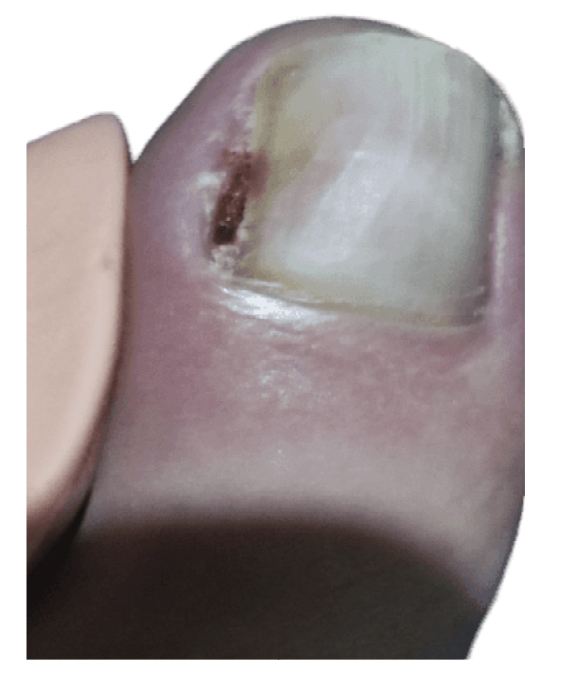

La paciente presenta inicialmente mejoría del dolor, aunque nunca termina de ceder completamente (Figura 4). Refiere recurrencia de la lesión ungueal lo que le lleva a consultar una segunda opinión a las 6 semanas de la intervención con otro podólogo. Este último con fecha 27 de diciembre (Figura 5) realiza cultivo bacteriano de la lesión, resultando negativo, y también valoración de la lesión mediante ecografía (sin informe). El 13 de enero la paciente es intervenida quirúrgicamente mediante técnica fenol-alcohol en el borde lateral del primer dedo del pie izquierdo (Figura 6).

Figura 4. Semanas 9-14. Recurrencia progresiva de la lesión tras resección parcial.

Figura 5. Semana 16. Cultivo bacteriano negativo y valoración por ecografía (no disponible).

Figura 6. Semana 18. Segunda intervención mediante matricectomía parcial con técnica fenol-alcohol.